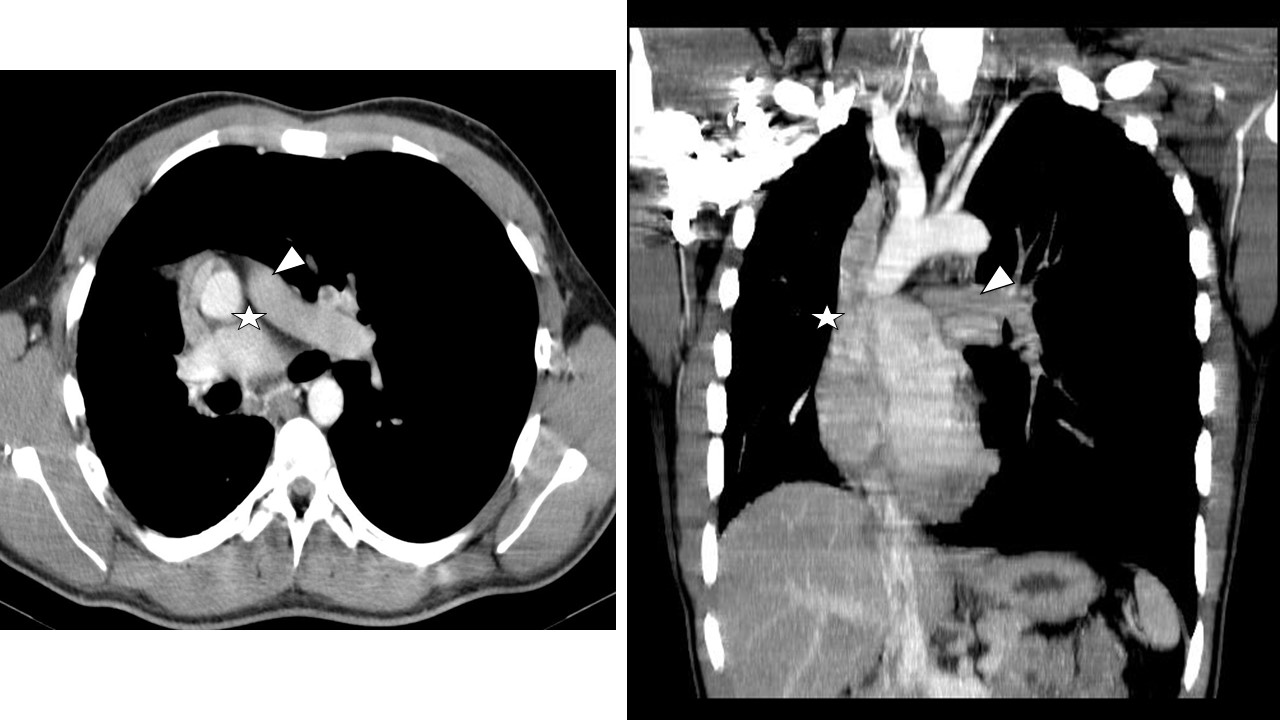

Quando o RX não esclarece completamente o quadro clínico ou há suspeita de complicações, a TC de alta resolução (TCAR) entra em cena. Ela permite observar com riqueza detalhes como espessamento septal, opacidades em vidro fosco, nódulos pulmonares, destruição alveolar e alterações brônquicas.

Com cortes finos e reconstruções multiplanares, é o exame de escolha para avaliar a extensão de uma fibrose, o padrão intersticial, ou confirmar/emergir lesões compatíveis com sequelas da COVID-19. Também auxilia no estadiamento de neoplasias pulmonares e investigações vasculares (angio-TC).